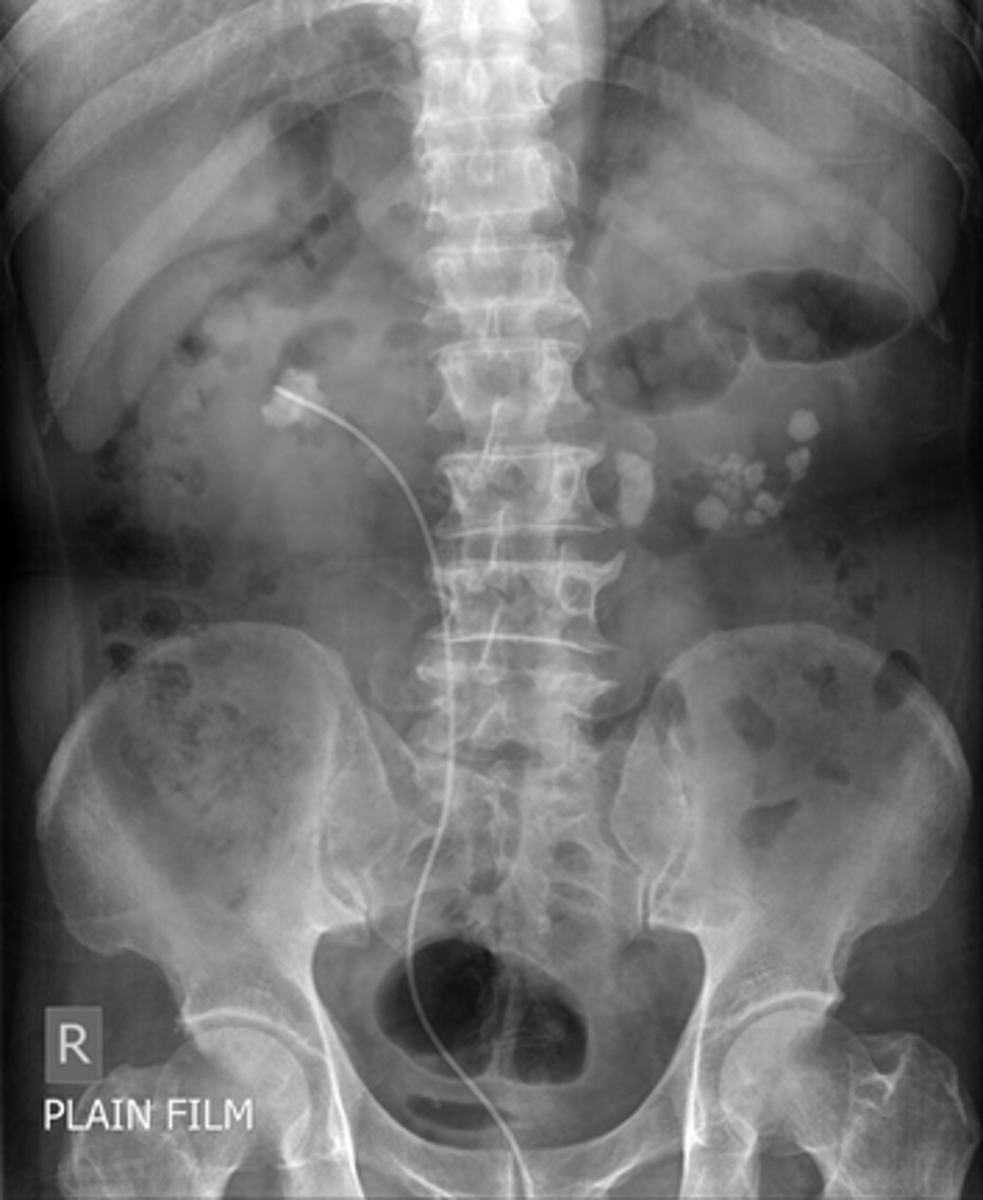

Ogilvie syndrome

- loss of peristalsis, resulting in sometimes massive dilatation of the entire colon, resembling a large bowel obstruction, as in this patient.

Ogilvie syndrome (acute intestinal pseudoobstruction) may occur in older adults who are usually already hospitalized or on chronic bed rest. Drugs with anticholinergic effects may cause or exacerbate the condition.